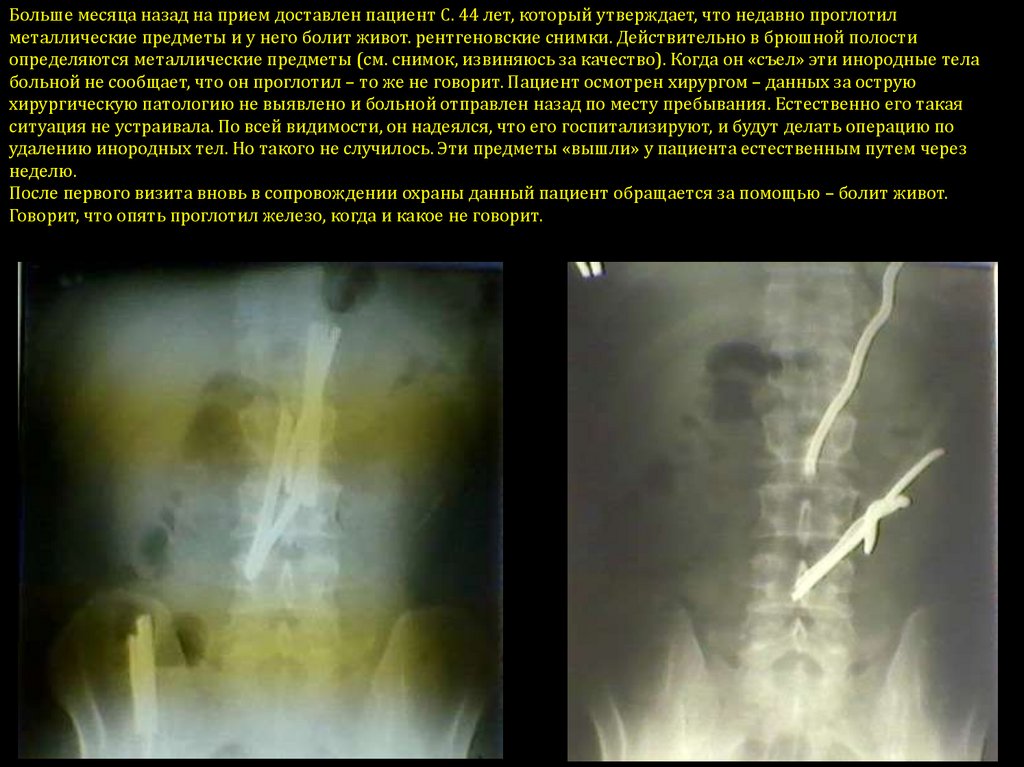

Необычные находки: инородные тела на рентгенограмме брюшной полости